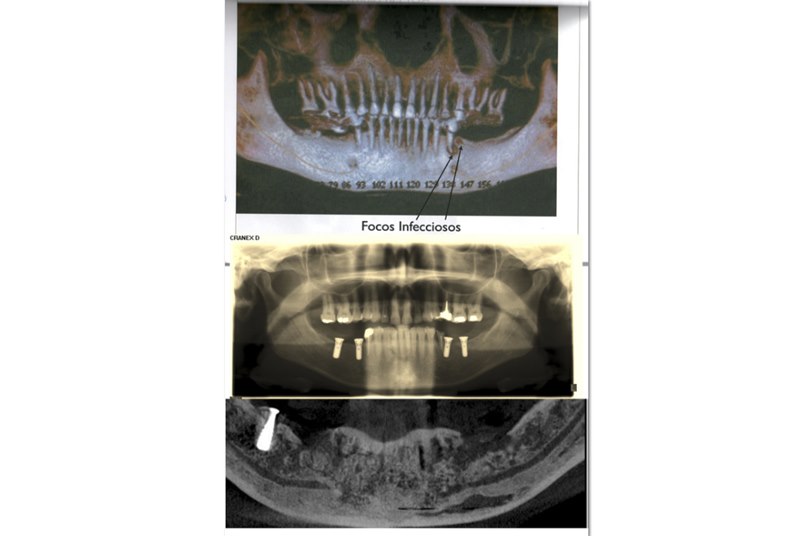

Así, tras acudir varias veces, exigió que le realizarán una radiografía, la cual no entiende porque no le realizaron tras la intervención para asegurarse de que todo estaba hecho correctamente. "En ella se veía como uno de los implantes estaba sobre el diente, pero la dentista me decía que no era así, que todo estaba bien y que era un efecto óptico", señala.

Así, la defensa de esta mujer presentó alegaciones a dicho informe, basándose en otro realizado por un médico forense de la Universidad de Las Palmas, que pone de manifiesto la supuesta negligencia médica. Sin embargo, a pesar de que esto fue en febrero, aún no ha recibido respuesta. En dicho documento no sólo se dice que a Leticia se le colocó un implante de forma incorrecta, sino que además ni siquiera debían habérselo puesto. "Se basaron en un TAC que tenía de 2009, cuando me tenían que haber hecho otro, pero aún así ahí ya se veía que tenía un foco de infección, por lo que ya de por sí no me deberían haber puesto el implante, que encima lo colocaron mal, encima de un diente", relata.

Además, dicho implante se lo colocaron en la pieza 34 cuando, en teoría, iban a colocárselo en la 36, hecho que aparece reflejado en el propio informe de la médico forense de los Juzgados. "Ahí mismo pone que iban a ponerlo en la 36, pero no lo pusieron ahí, y eso es evidente, pero no lo dice. Sin embargo, sí que dice que rechacé los implantes, cuando es mentira, porque aún tengo uno y que fue la clínica quien me llevó al hospital, cuando fue mi hermana", apunta.